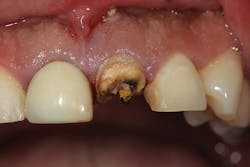

Although unpredictable, a greater amount of alveolar ridge loss following extraction usually occurs in the horizontal dimension and affects the buccal bone of the ridge.3 In fact, 50% of alveolar bone dimension can be lost after tooth extraction, with losses reported of up to 6–7 mm (figure 1). Two-thirds of this loss of bone volume can occur within the first three months of tooth extraction.4